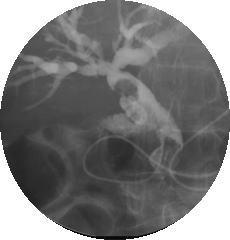

バスケットカテーテルによる胆管結石の除去

エコー上、総胆管内にφ10mm前後のmassをみる。

ERCP

*1を施行したところ、総胆管内に腹部エコーと一致した胆管結石(Photo-1)が認められた。

EST*2を施行し、バルーンカテーテル(Photo-2)及びバスケットカテーテル(Photo-3)で排石(Photo-4)を行った

(Photo-1)胆管結石 (Photo-2)バルーンカテーテル

(Photo-3)バスケットカテーテル (Photo-4)除去